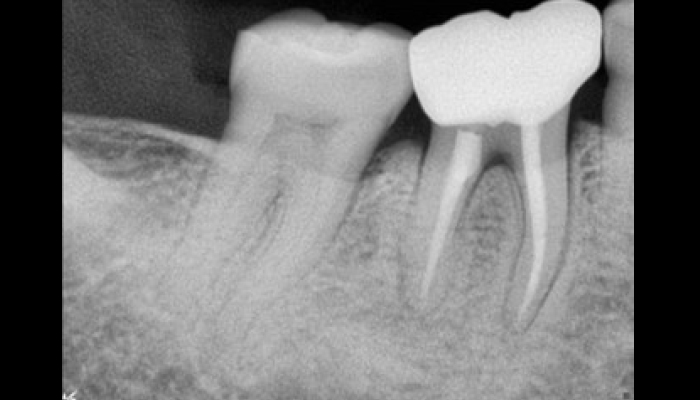

Before

로그인 후 이용해주세요

After

양쪽 아래 어금니 충치 치료

황OO님 전후사진 / 치료 기간 : 당일 / 레진, 인레이

Before

로그인 후 이용해주세요

After

어금니 신경치료

주OO님 전후사진 / 치료 기간 : 당일 / 재근관치료

Before

로그인 후 이용해주세요

After

양쪽 아래 어금니 충치 치료

박OO님 전후사진 / 치료 기간 : 당일 / 레진, 인레이

Before

로그인 후 이용해주세요

After

어금니 신경치료

김OO님 전후사진 / 치료 기간 : 당일 / 재근관치료